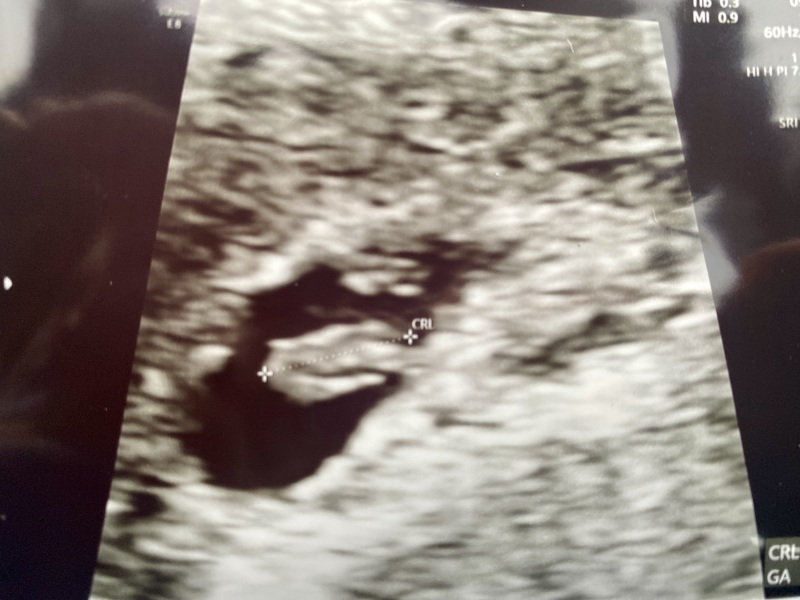

Isitisit · 20/12/2023 11:25

Hi all! I had my early scan and booking appt today.

Baby is measuring 6w+3. Slightly overwhelmed with the number of appointments they said I will have (high risk pregnancy) but am glad they are monitoring. Felt very weird to see the little heartbeat!